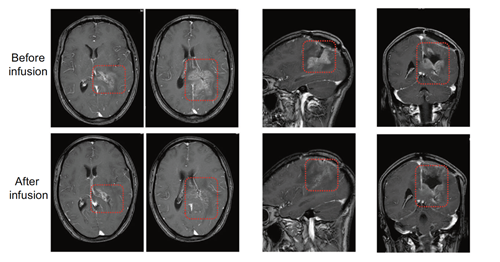

查看详情中枢神经系统恶性肿瘤,特别是胶质瘤、转移瘤等具有发病率高、侵袭性生长、预后不佳等特点。一旦复发,相应治疗选择非常有限,预后不佳且伴随着很大的副作用。CAR-T作为一种新兴的免疫治疗手...